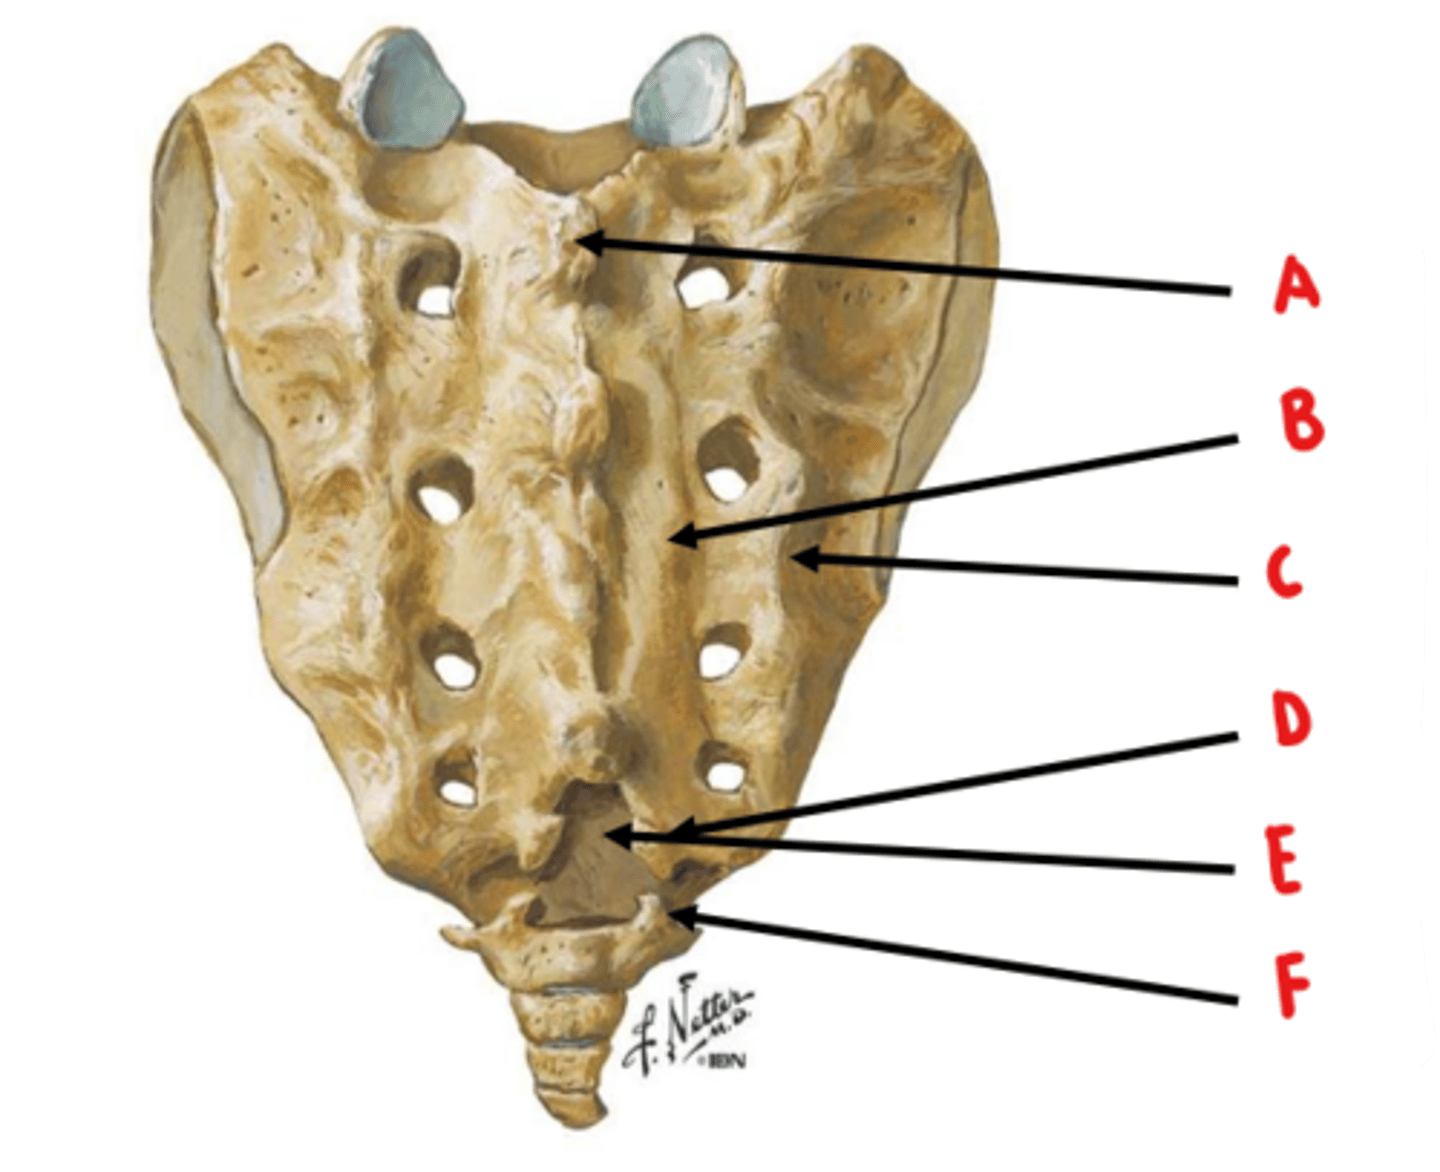

median sacral crest

Identify A

medial sacral crest

Identify B

lateral sacral crest

Identify C

sacral cornua

Identify D

sacral hiatus

Identify E

coccygeal cornua

Identify F

anterior sacral foramen = ventral rami

posterior sacral foramen = dorsal rami

ventral rami are larger because they innervate a larger area of tissue

What structures exit through the anterior and posterior sacral foramen? Which is larger and why?